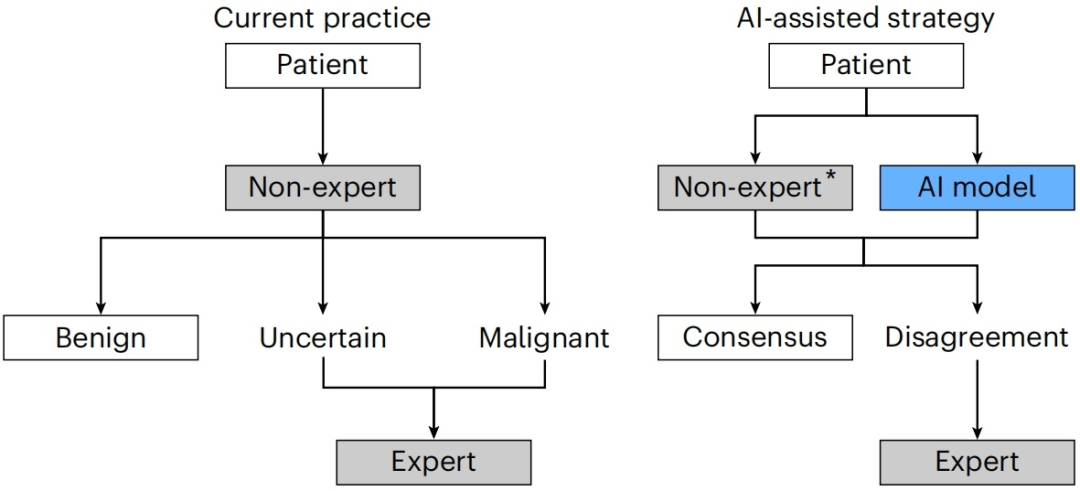

该研究基于其构建的超声图像卵巢病变辅助诊断模型提出了分诊策略,为AI模型如何融入临床诊断流程提供了宝贵见解。在此策略下,首先由AI模型和初级超声检查人员分别进行诊断,在诊断结果不一致时再由资深超声检查人员介入,能够有效缓解资深超声检查人员的工作压力。